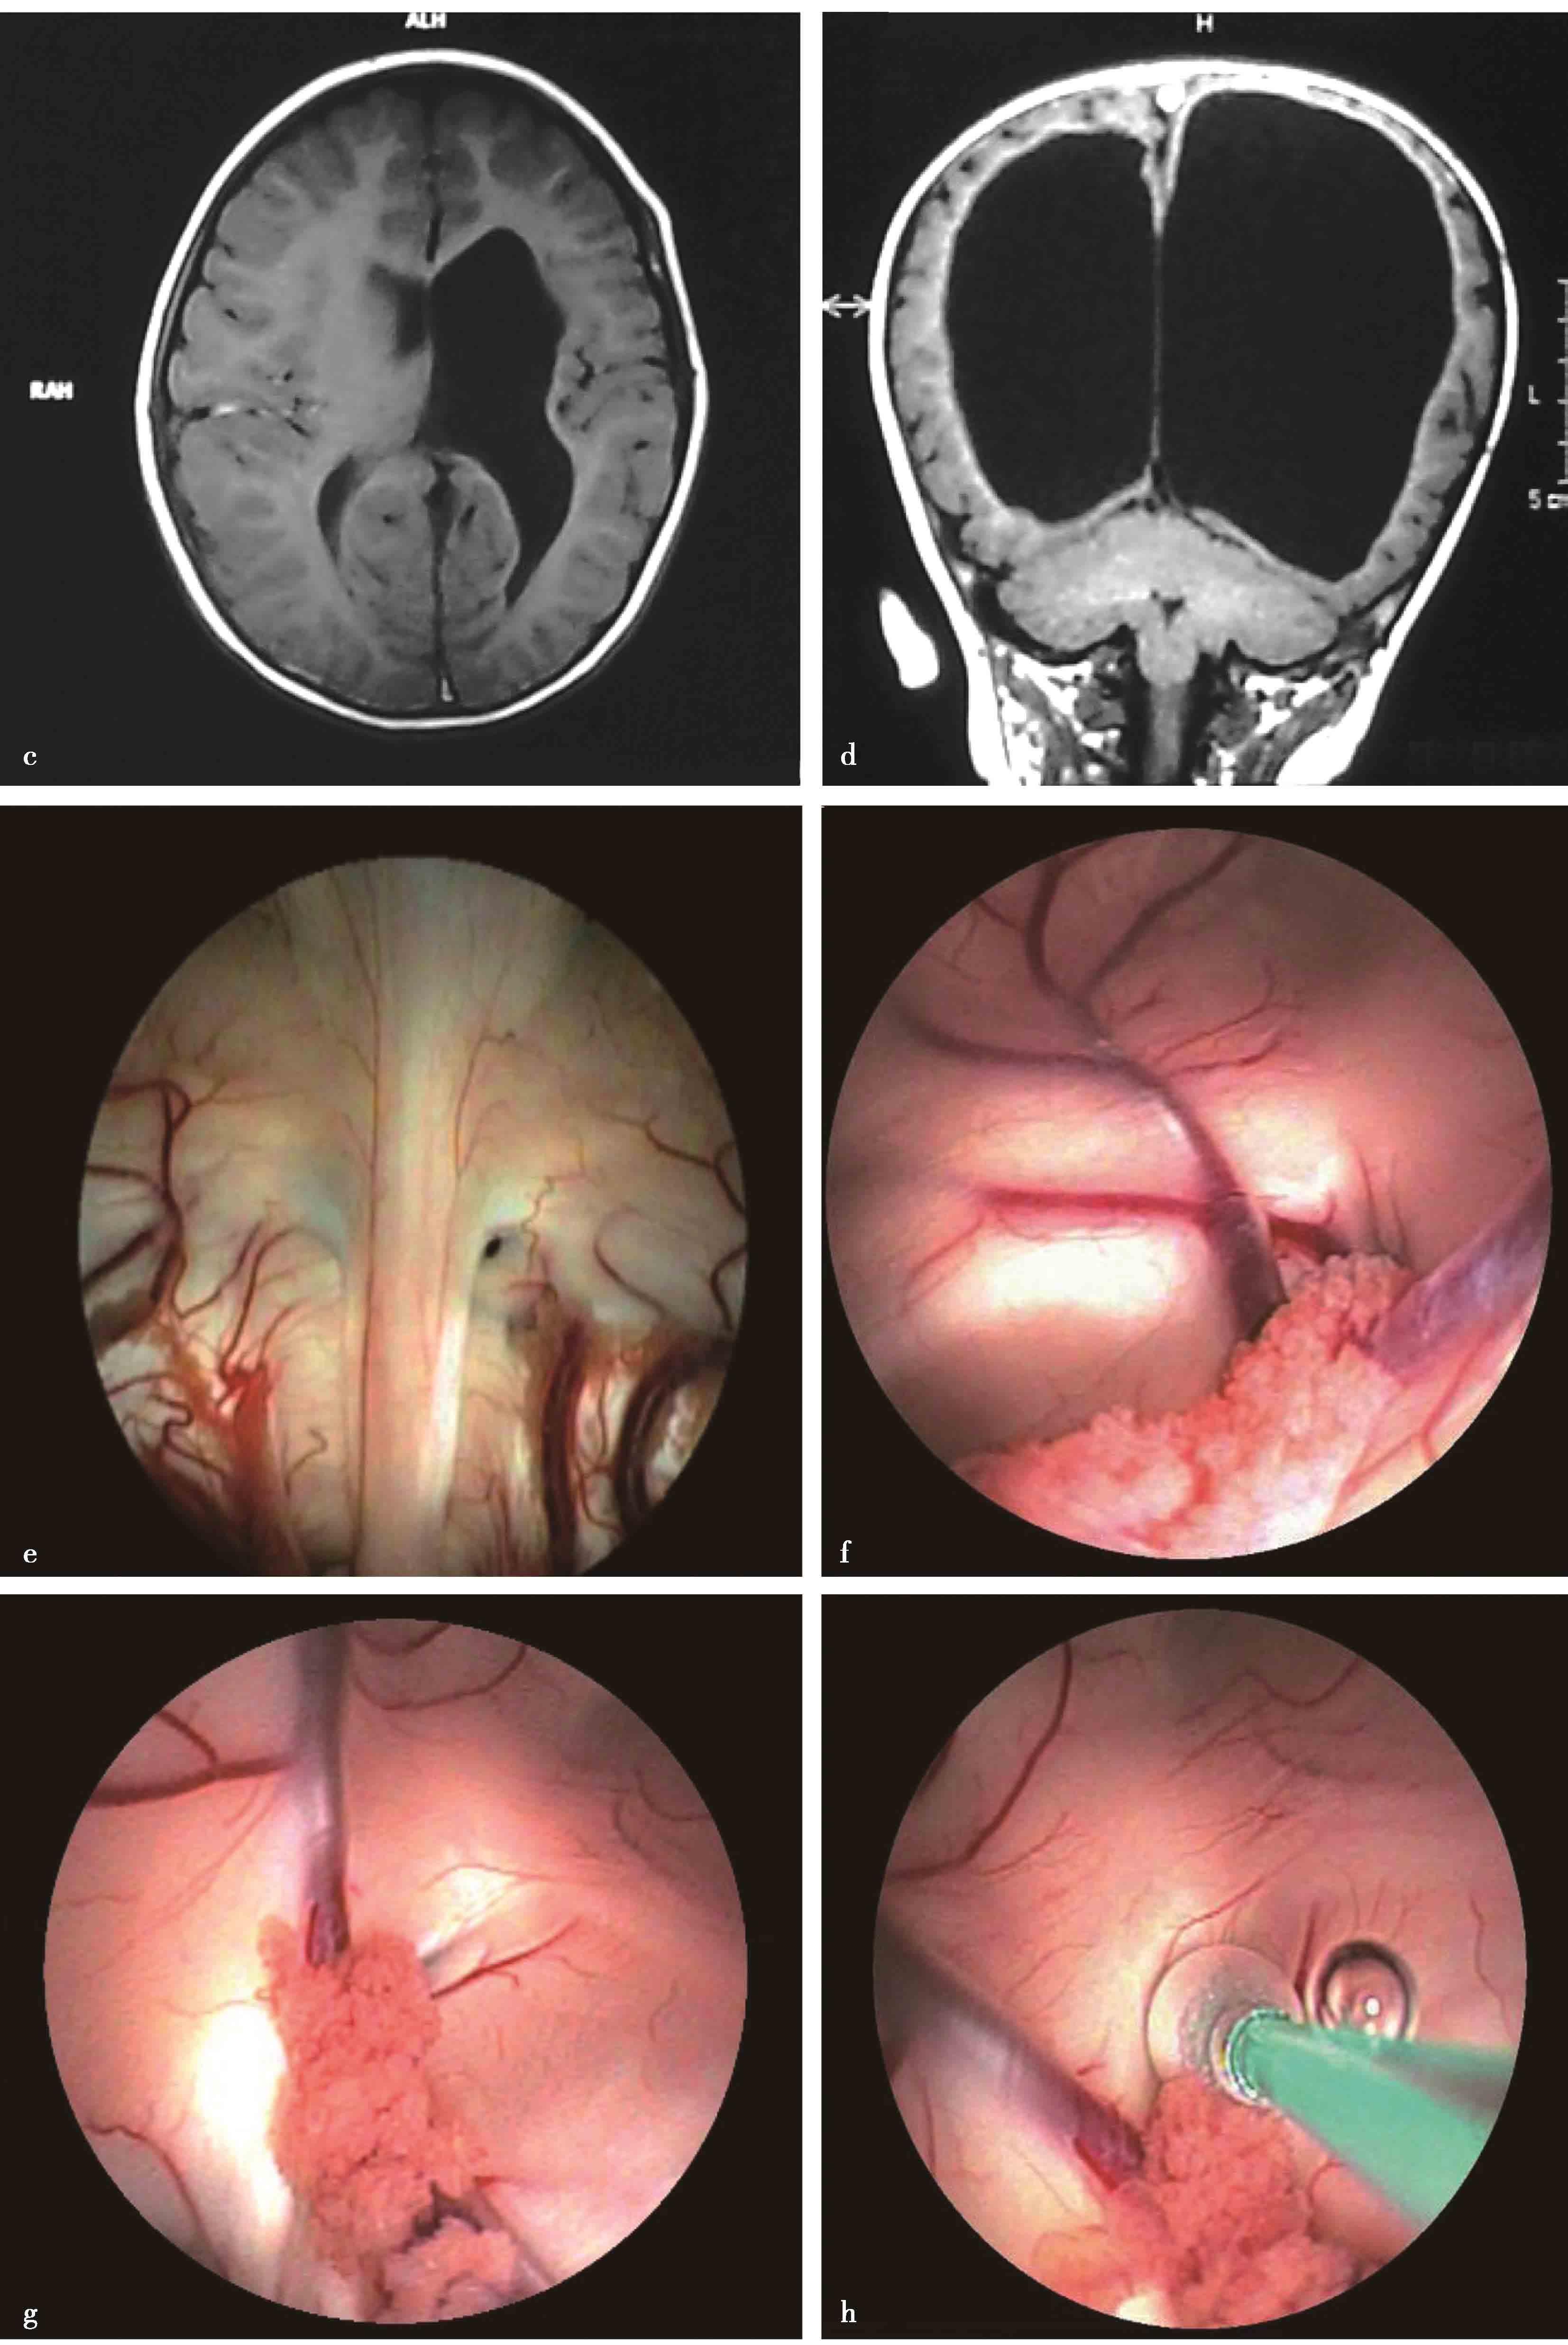

图3-1-1-1 出血后脑积水的脑室演变

a.发病时头颅CT:脑室内血肿呈高密度;b.发病12天后复查CT:血肿已呈低密度;c.发病5个月后头颅MRI:脑室明显扩张,脑室内未见异常信号;d.内镜下探查见脑室内仍有陈旧血斑及含铁血黄素沉积

图3-1-1-2 第三脑室底下疝的神经影

a.头颅MRI矢状位片所见,酷似鞍上池囊肿;b.内镜下探查,证实长期脑积水所致第三脑室底深度下疝

图3-1-1-3 内镜下脑室探查,明确导

a.头颅磁共振矢状位片提示导水管梗阻;b.内镜下探查证实导水管内肿瘤

图3-1-1-4 感染后脑积水内镜下探查所见

a.脑室壁上的菌斑;b.脑室内结核所致干酪样坏死物;c.脑室内真菌感染;d.第四脑室内囊虫